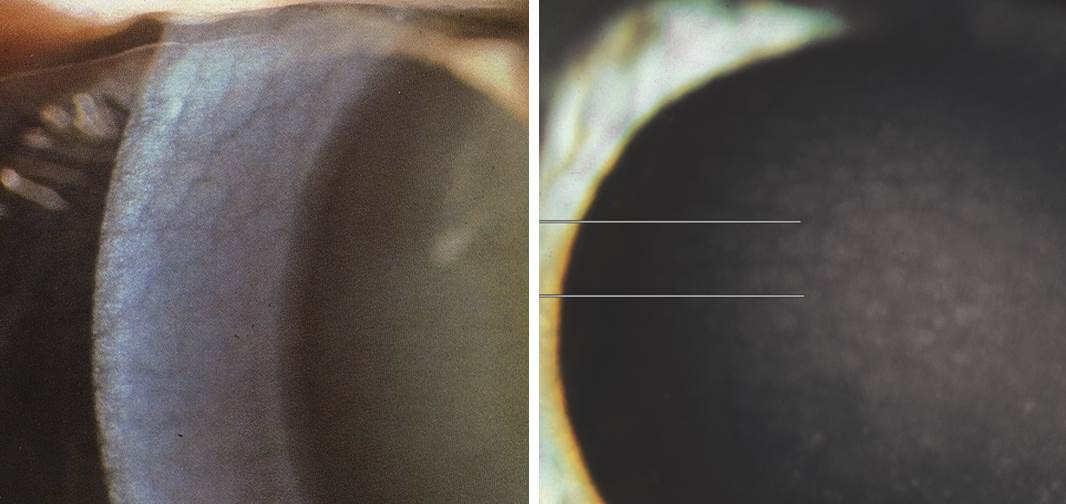

노인환 (Arcus senilis)

양안이 대칭적이고 나이가 들면서 수년에 걸쳐 서서히 진행되는 퇴행성변화입니다. 여자보다 남자에서 흔하고 모든 남성의 2/3이 40-60대에 노인환을 보이고 80세경에는 거의 100% 노인환이 나타납니다.

원인 : 각막주변부의 지방침착으로 아래쪽에 황백색으로 시작해서 위쪽으로 진행되어 원형이 됩니다. 지방성분은 데스메막 위쪽에 침착되고 이후 보우만층에 침착되며 진행되면 기질에 위치하지만 윤부는 보존됩니다. 혈관으로부터 생기며 콜레스테롤, 콜레스테롤에스테르, 인지질, 중성지방으로 구성되어 있습니다.

편측환 : 한쪽눈에만 노인환이 있는경우는 환이 없는쪽 눈의 경동맥 폐쇄 (혈류량 감소로인해 지방침착이 안됨) 또는 환이 있는쪽의 저안압증의 가능성이 있어 주의가 필요합니다.

40세 이하에서 노인환을 가진 환자의 경우 고지혈증 2,3형에 대한 검사가 필요하고 심장질환의 위험성이 증가합니다.

치료 : 시력에 영향이 없고 노화 현상으로 치료가 필요하지 않습니다.